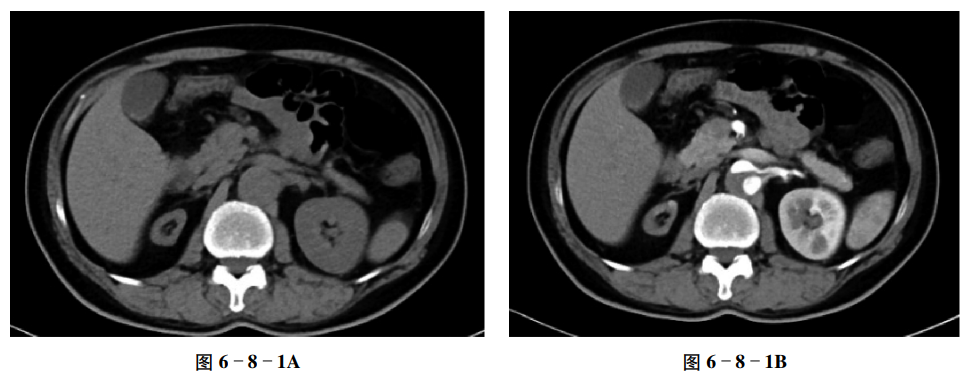

【CT征象】

平扫示右肾明显缩小,外观仍保持正常肾的形态,左肾代偿性增大(图6-8-1A),增强扫描示双肾皮质明显强化,髓质密度稍低,右肾的形态及排泄功能与左肾相似(图6-8-1B、C)。腹主动脉见夹层形成。

【重要征象】

右肾体积小,肾皮质和髓质密度、强化相对正常,"肾缩影征"。

CT表现

①多为单侧,表现为肾区小的软组织影,其肾实质、肾窦普遍缩小,可见肾盂,如正常肾的"缩影"。②肾动脉及输尿管细小,增强扫描肾实质强化,可见肾盂、肾盏内对比剂影。③对侧肾代偿性增大,皮质明显增厚。